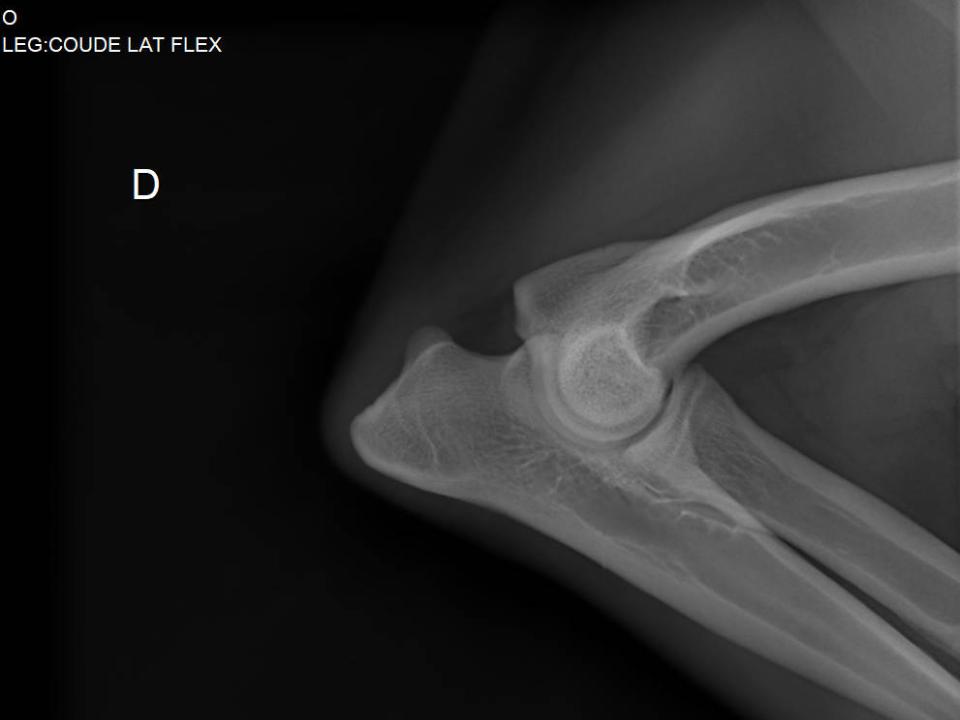

Radiographie Ollie suivi arthrose antérieur droit Gatavet 09/2025

Un examen vétérinaire avec radiographie permettra de confirmer ou non le diagnostic.